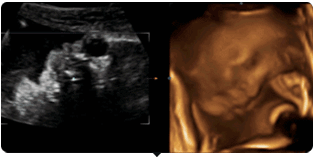

四维彩超就是四维成像技术(4D),能直观,立体显示人体器官的三维结构及动态、实时地观察立体结构。主要可以进行胎龄检测、分析胎儿的发育情况、筛查胎儿畸形等。

单胎为怀孕第20—28周,双胞胎为18-22周。因为这个时期的胎儿大小适中,羊水量充足,比较容易采集到相对清晰的图像。

四维彩超动图欣赏

好困,打哈欠